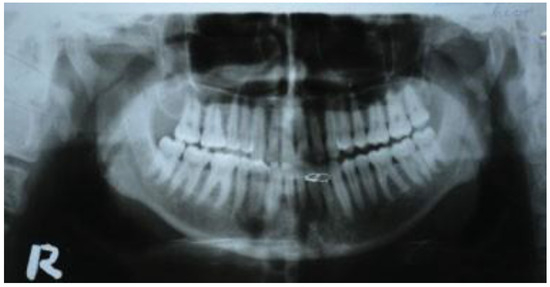

Six out of seven patients showed good anatomical reduction on postoperative CT scans (Figure 6, Figure 7, Figure 8 and Figure 9) and orthopan-tomograph (Figure 10, Figure 11, Figure 12 and Figure 13). On regular follow-up at 3 weeks, 3 months, and 6 months, and 1 year, no evidence of wound dehiscence, discrepancy in occlusion, or lower border malalignment was seen (Figure 14).

Figure 10. Case 1: Preoperative orthopantomograph showing interforaminal mandible fracture of right side.